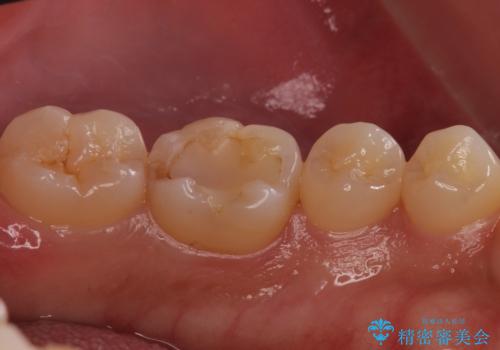

奥歯が欠けた セラミックインレーでの治療

- 奥歯が欠けたとのことで来院されました。

白い詰め物をご希望されたため、セラミックインレーでの治療を行います。

治療前後で比べると、詰め物と歯の間のすき間もなくなりセラミックインレーの適合の良さが伺えます。